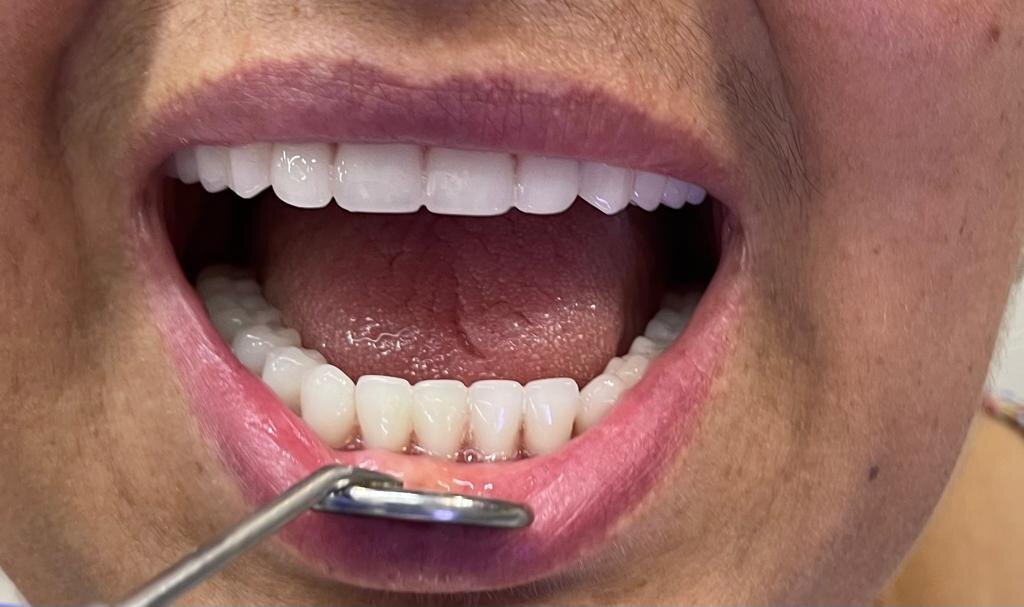

Фотогалерея